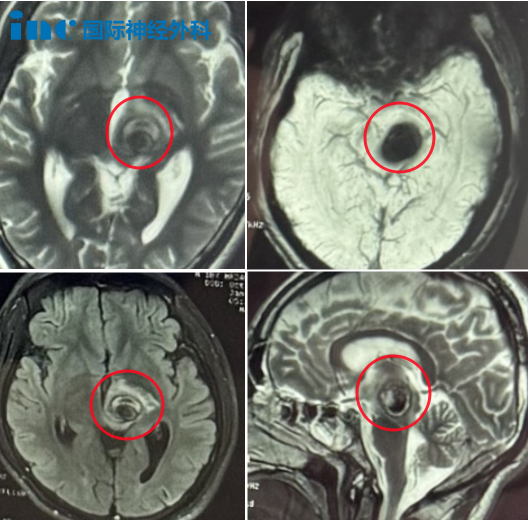

2024年1月7日,小林第2次出血

術前術后MRI影像

小林的海綿狀血管瘤正生長在腦干中腦部位,這處于腦干上端,介于腦橋和間腦之間。人的中腦長度約僅15~20mm。所有大腦皮層與脊髓間的上行及下行神經(jīng)通路都經(jīng)過中腦,同時,中腦通過白質(zhì)與其他中樞神經(jīng)系統(tǒng)的分部相聯(lián)系,中腦的病變治療難度大,難以手術,手術風險極大。